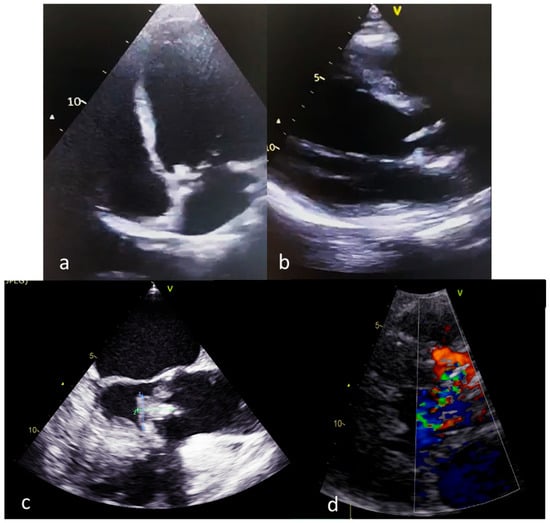

- Lupu, S.; Pop, M.; Mitre, A. Loeffler Endocarditis Causing Heart Failure with Preserved Ejection Fraction (HFpEF): Characteristic Images and Diagnostic Pathway. Diagnostics 2022, 12, 2157. [Google Scholar] [CrossRef]

- Todde, G.; Gargiulo, P.; Canciello, G.; Borrelli, F.; Pilato, E.; Esposito, G.; Losi, M.A. Rapid Evolution of an Aortic Endocarditis. Diagnostics 2022, 12, 327. [Google Scholar] [CrossRef]